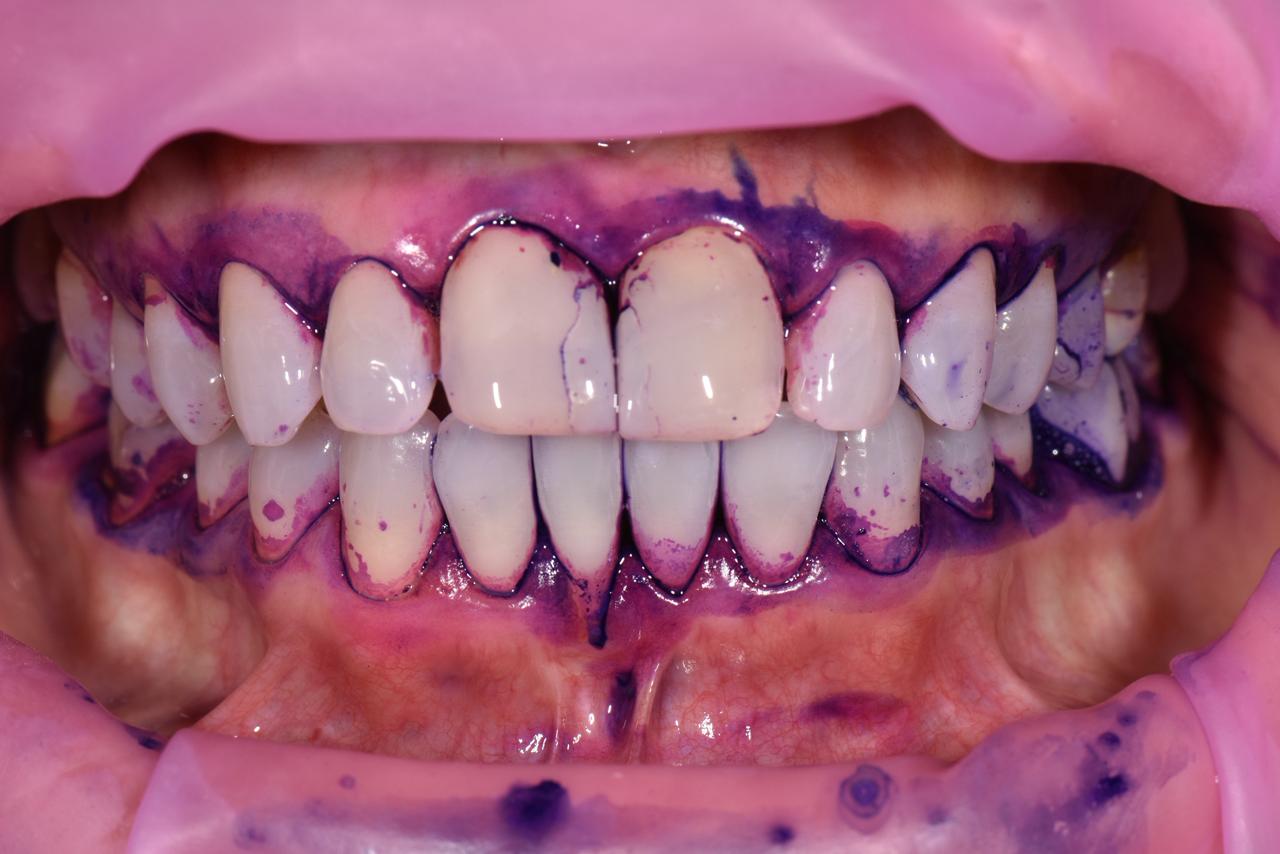

La gingivitis es la forma más común y temprana de enfermedad de las encías. Se caracteriza por la inflamación, enrojecimiento y sangrado de las encías debido a la acumulación de placa bacteriana alrededor de los dientes.

Aunque suele ser indolora y reversible, si no se trata a tiempo, puede evolucionar hacia una periodontitis, una forma más grave que puede comprometer el hueso y los tejidos que sostienen los dientes.